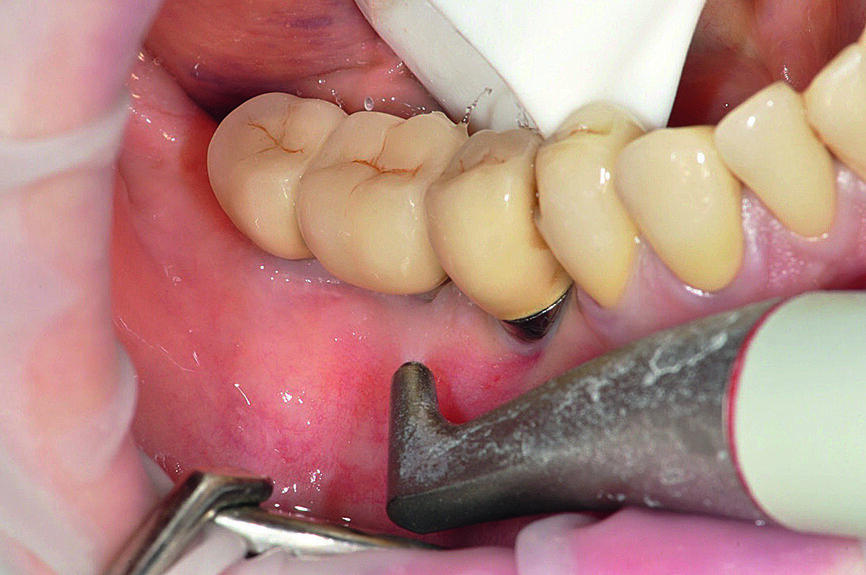

Figs. 1a : Implant en position 14 affecté par une péri-implantite : sondage péri-implantaire avec la couronne prothétique in situ

Fig b : Implant en position 14 affecté par une péri-implantite : sondage péri-implantaire après retrait de la couronne prothétique.